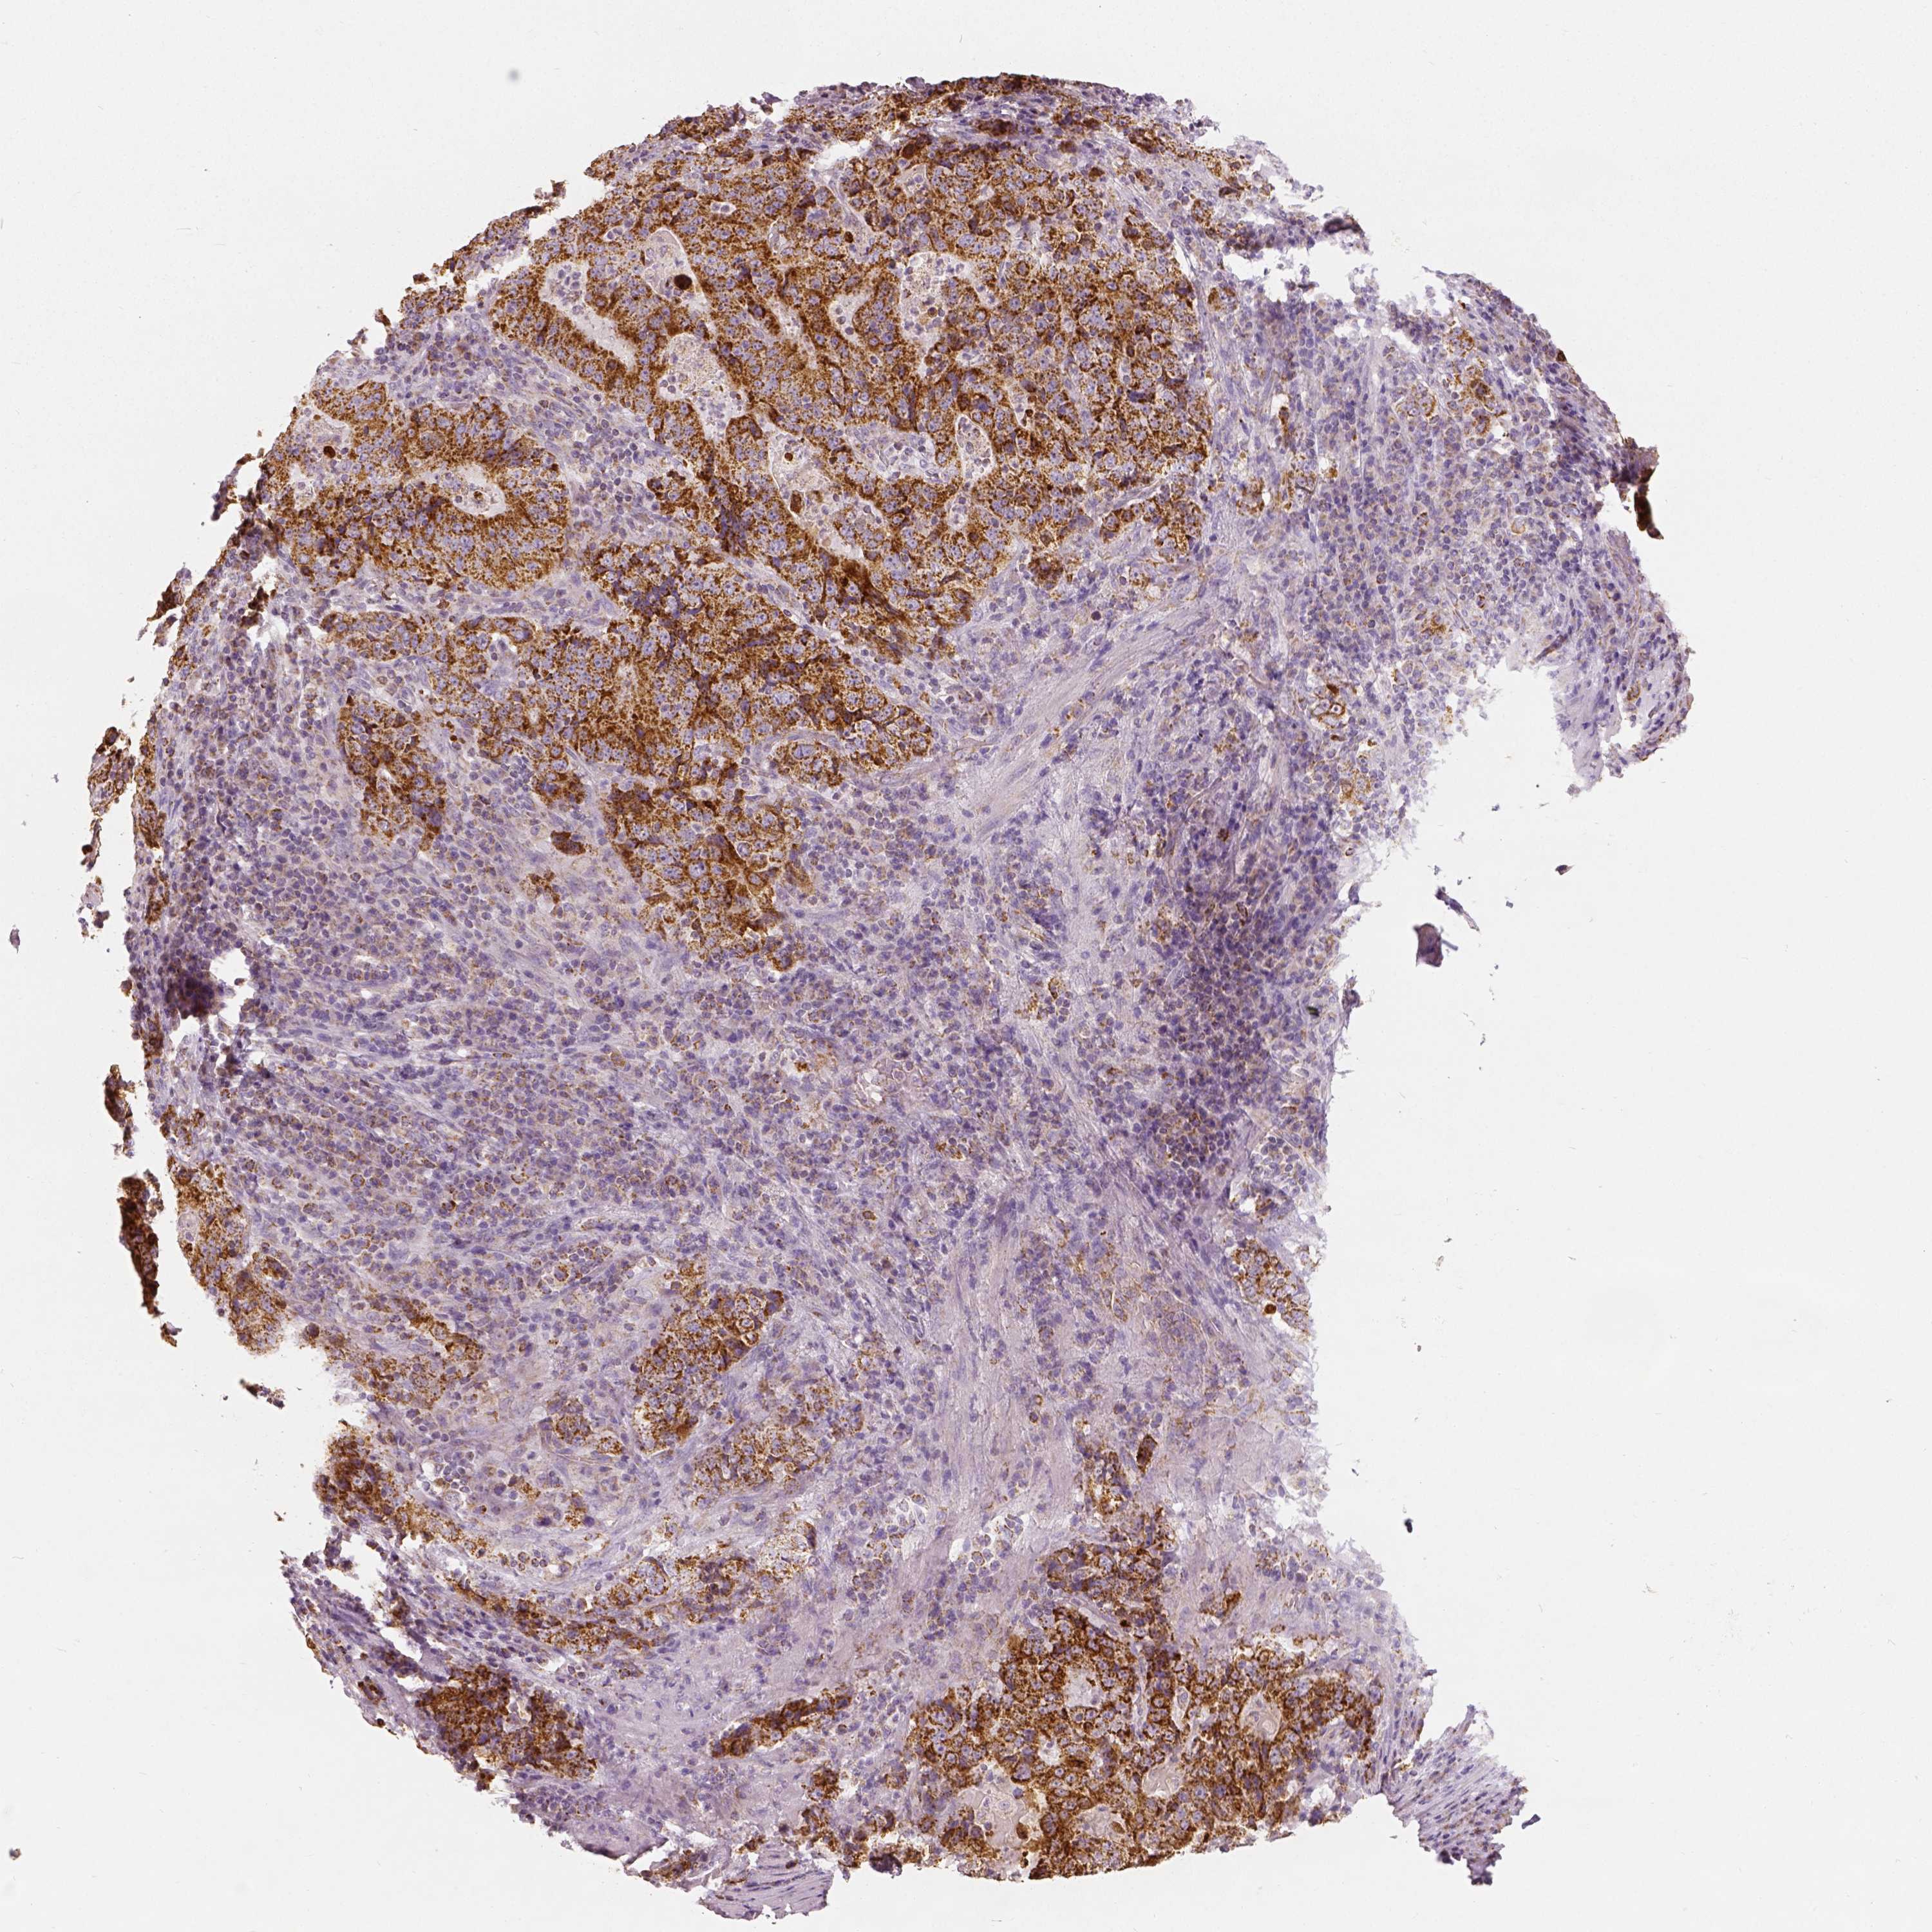

STOMACH CANCER - Protein expressioni

A mouse-over function shows sample information and annotation data. Click on an image to view it in a full screen mode. Samples can be filtered based on level of antibody staining by selecting one or several of the following categories: high, medium, low and not detected. The assay and annotation is described here.

Note that samples used for immunohistochemistry by the Human Protein Atlas do not correspond to samples in the TCGA dataset.

Antibody stainingi

Antibody staining in the annotated cell types in the current human tissue is reported as not detected, low, medium, or high, based on conventional immunohistochemistry profiling in selected tissues. This score is based on the combination of the staining intensity and fraction of stained cells.

Each image is clickable and will lead to virtual microscopy that enables deeper exploration of all samples and also displays staining intensity scores, fraction scores and subcellular localization as well as patient and tissue information for each sample.

Antibody HPA036978

Antibody HPA036979

Antibody CAB068215

Staining

High

Medium

Low

Not detected

Intensity

Strong

Moderate

Weak

Negative

Quantity

>75%

75%-25%

<25%

None

Location

Nuclear

Cytoplasmic/membranous

Cytoplasmic/membranous,nuclear

Adenocarcinoma, NOS